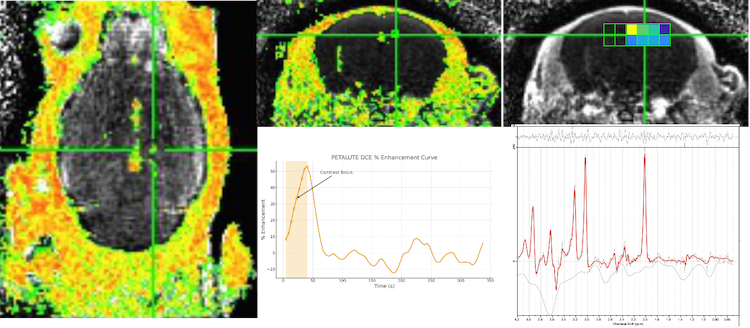

Figure 1: Dual-echo sodium balanced steady-state free precession (bSSFP) PETALUTE acquisition on a 3T Siemens Prisma system. Left: First-echo sodium bSSFP PETALUTE images highlighting short-T₂ sodium components and higher signal intensity in regions with rapid transverse relaxation. Right: Second-echo PETALUTE sodium images demonstrating reduced short-T₂ contribution and enhanced long-T₂ contrast. Multi-planar views (coronal, sagittal, axial) illustrate echo-dependent sodium signal distribution across the brain. Image: University of North Carolina at Chapel Hill’s Biomedical Research Imaging Center, Chapel Hill, N.C.

The PETALUTE sequence is a novel method that helps accelerate MRI by enabling quantitative, artifact-resistant imaging at the molecular and cellular levels. The development and validation of the PETALUTE acquisition strategy for high-resolution, multi-contrast imaging of both 1H and X-nuclei signal components enhances sensitivity, minimizes artifacts and facilitates detailed visualization of short-transverse relaxation time species and metabolic processes crucial to translational neuroscience and disease modeling (Figure 1). It combines multi-nuclear compatibility, UTE, and robust self-gating to build a versatile platform for examining tissue microstructure, ionic environments, and dynamic metabolic activities.